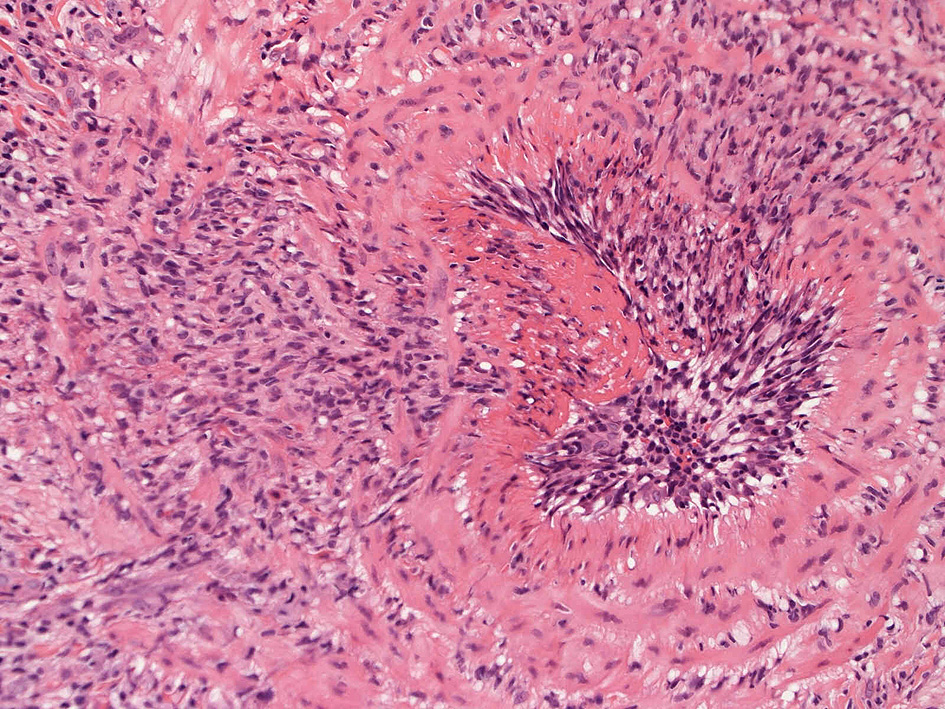

皮膚の血管(静脈・細動脈)病変、脂肪織炎 (サムネイルをクリックすると大きな画像が見られます)

Bec01.jpg

fibrinoidnecrosis01.jpg

vasculitisYa.jpg

fibrinoid necrosis

obstruction.jpg

免疫染色:血管腔を閉塞する細胞の多くはCD68, CD163陽性細胞. CD34陽性内皮が保たれている。